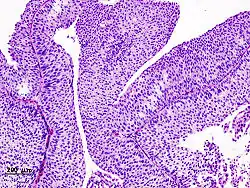

The 1973 WHO grading system for transitional cell carcinomas (papilloma, G1, G2 or G3) is most commonly used despite being superseded by the 2004 WHO[14] grading for papillary types (papillary neoplasm of low malignant potential [PNLMP], low grade, and high grade papillary carcinoma). High-grade carcinoma typically displays more pleomorphism, multiple mitoses, euchromatin and relatively prominent nucleoli, and uneven distribution of nuclei.

12. ^ Image is taken from following source, with some modification by Mikael Häggström, MD:

- Schallenberg S, Plage H, Hofbauer S, Furlano K, Weinberger S, Bruch PG; et al. (2023). "Altered p53/p16 expression is linked to urothelial carcinoma progression but largely unrelated to prognosis in muscle-invasive tumors". Acta Oncol. 62 (12): 1–10. doi:10.1080/0284186X.2023.2277344. PMID 37938166.{{cite journal}}: CS1 maint: multiple names: authors list (link)

13. ^ Source for role in distinguishing PUNLMP from low-grade carcinoma:

- Kalantari MR, Ahmadnia H (2007). "P53 overexpression in bladder urothelial neoplasms: new aspect of World Health Organization/International Society of Urological Pathology classification". Urol J. 4 (4): 230–3. PMID 18270948.